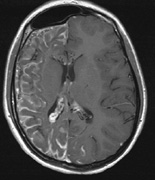

Optic nerve gliomas may involve the optic chiasm and be associated with endocrine disorders or nystagmus.68–70 Surgical excision of chiasmal gliomas (Fig. 6) carries a high risk of visual loss. Invasion of the hypothalamus or the third ventricle carries a poor prognosis, with greater than 50% 15-year mortality rate.71 One review of radiation treatment for chiasmal gliomas collated data from small case series and found no significant long-term improvement in visual function, progression, or mortality with radiation treatment.71 Other reports suggest that radiation doses over 4500cGy improve symptoms and slow progression of chiasmal gliomas over several years.72 Adequate tumor coverage by radiotherapy results in irradiation of normal brain and nearly all children need hormone replacement.73 Chemotherapy is an alternative.74,75

|